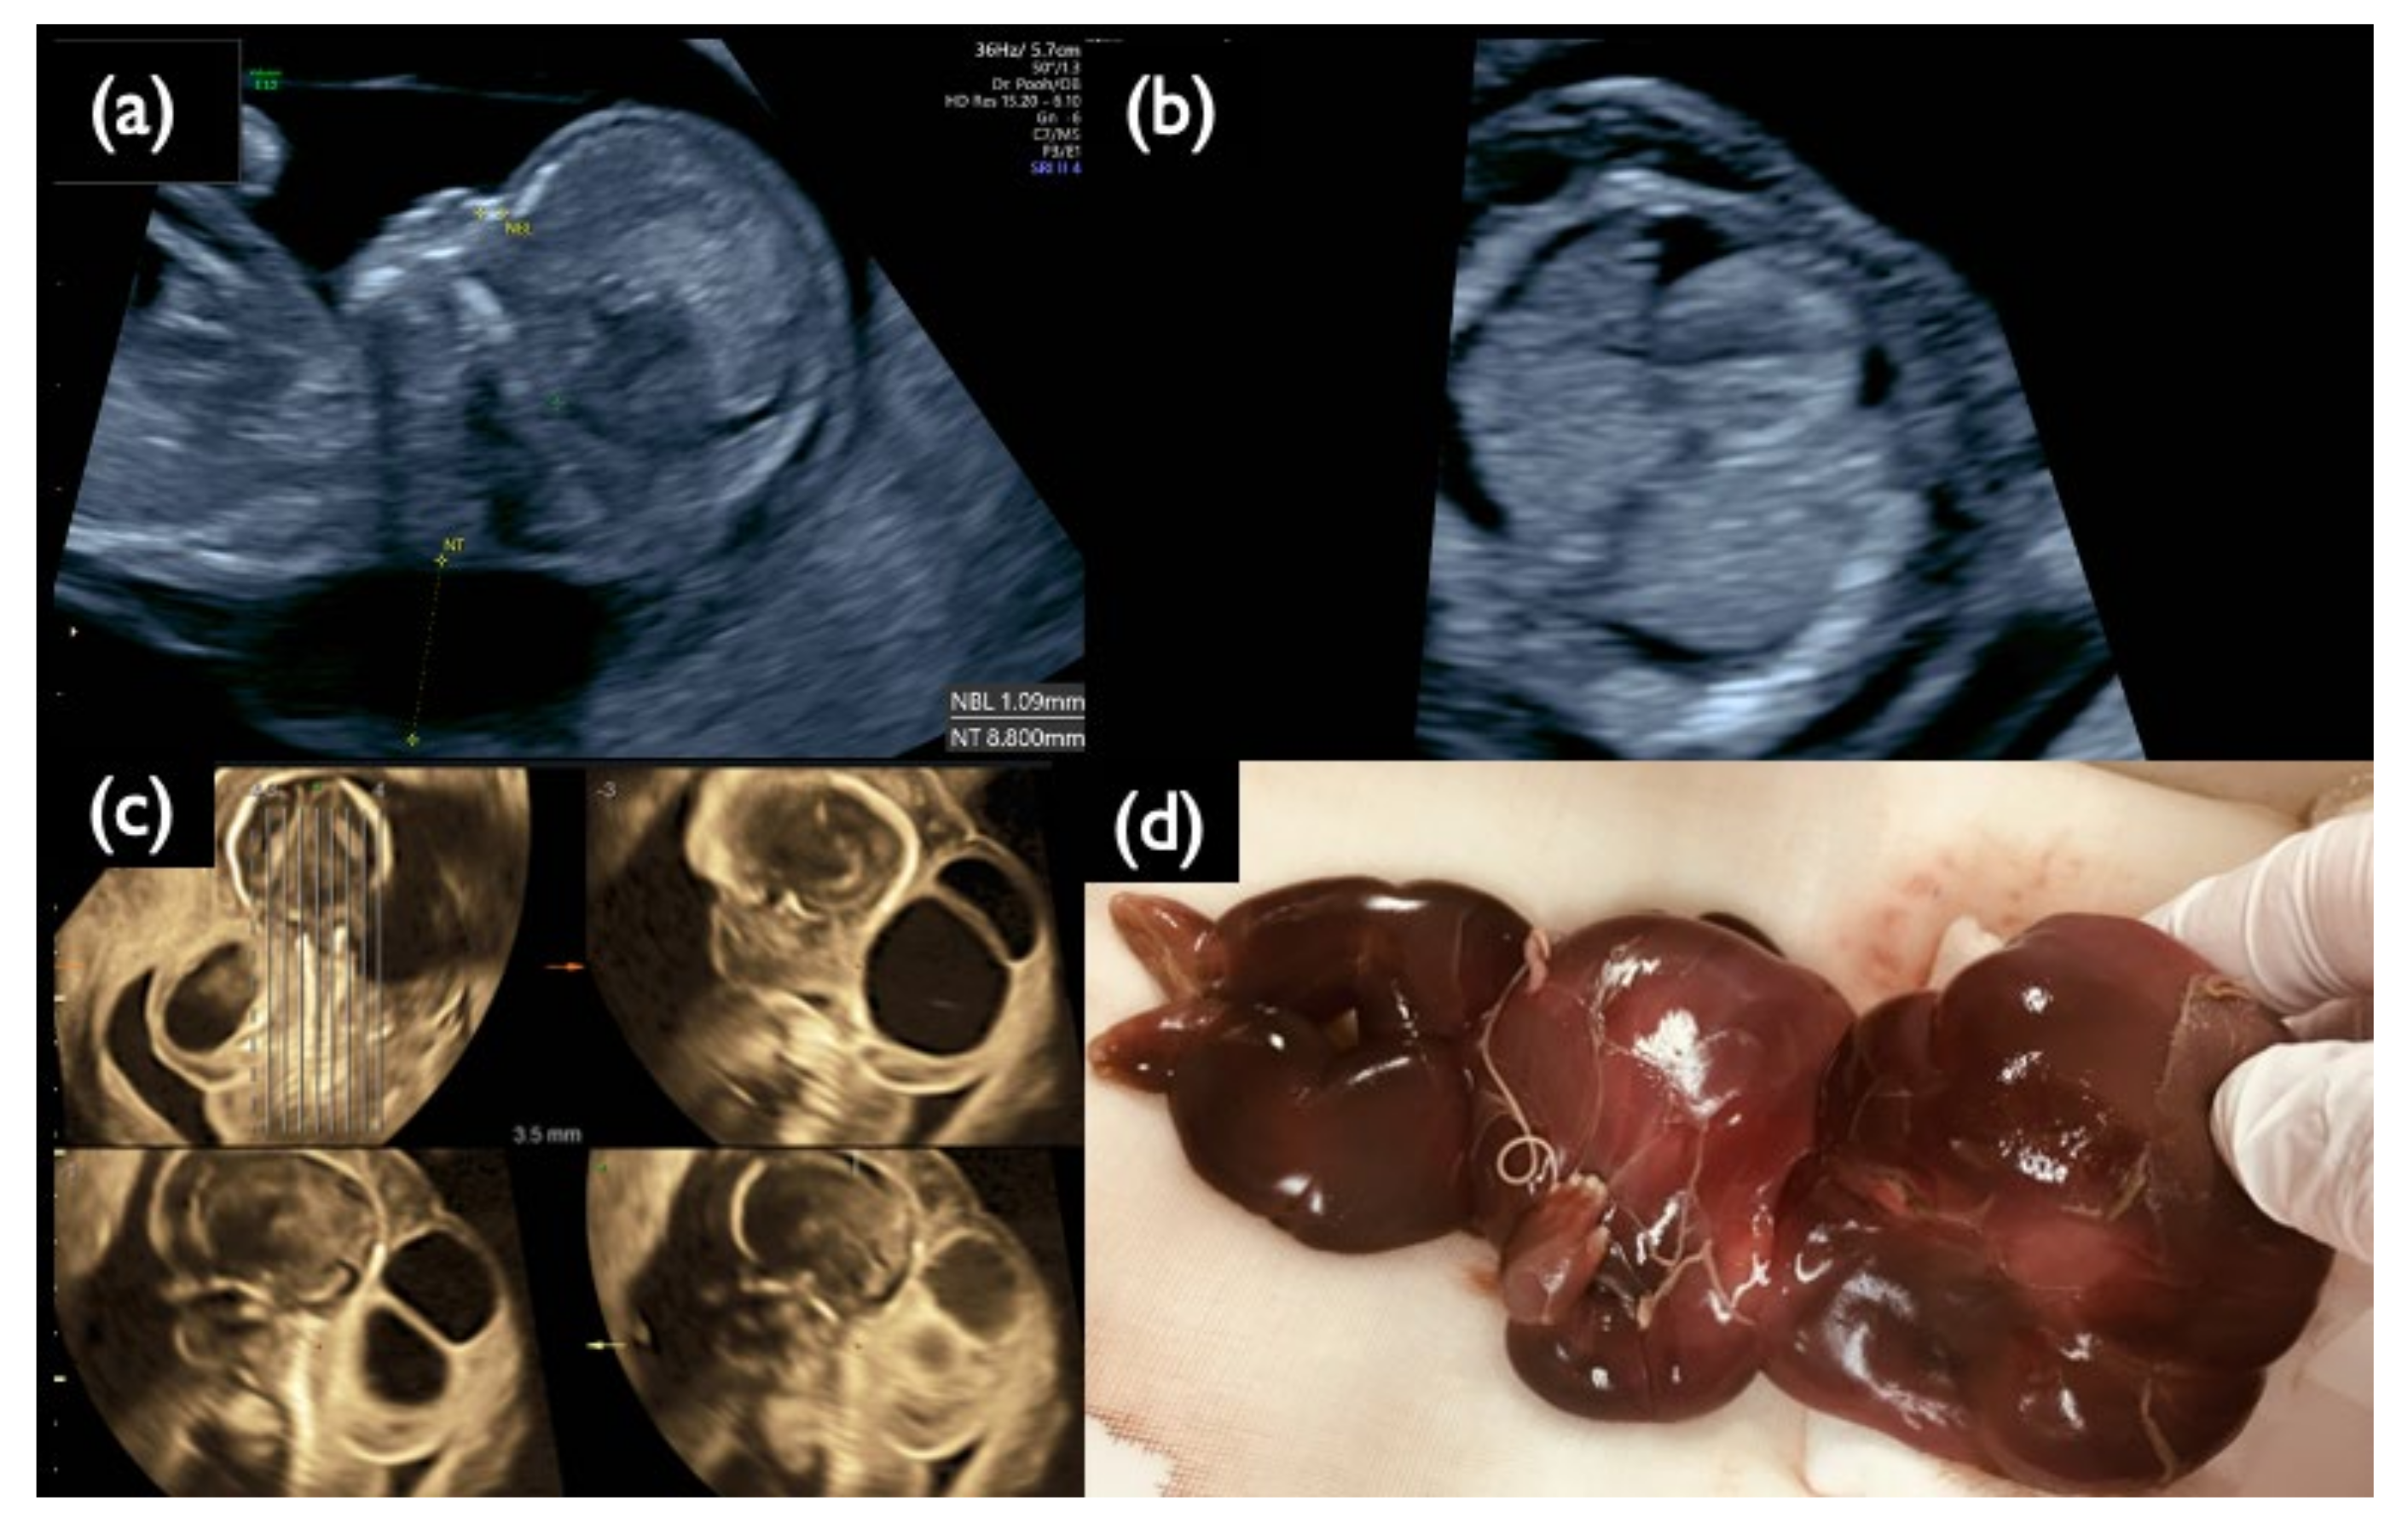

| Chromosome 18 relevant mosaicism | Mo5 | 13 + 5 | XX,+18 Mosaicism | T18 (56%) | 47,XX,+18/46,XX (44%/56%) | – | – | T18 Negative | 2.09 | + | 8.3 | Increased NT, GE moderate, Small NB, Micrognathia, Lowset ear, T18 like profile, Wrist contracture bilateral, Cardiomegaly, Large VSD, TR severe, MR severe, Stomach invisible, Hyperechoic bowel, DV reversed flow, SUA, Umb.A.reverse, T18 is strongly suspected, |